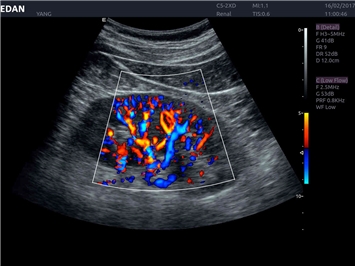

• Общей визуализации

Трехмерная реконструкция ЦДК:

Да

Энергетический допплер:

Color 3D: